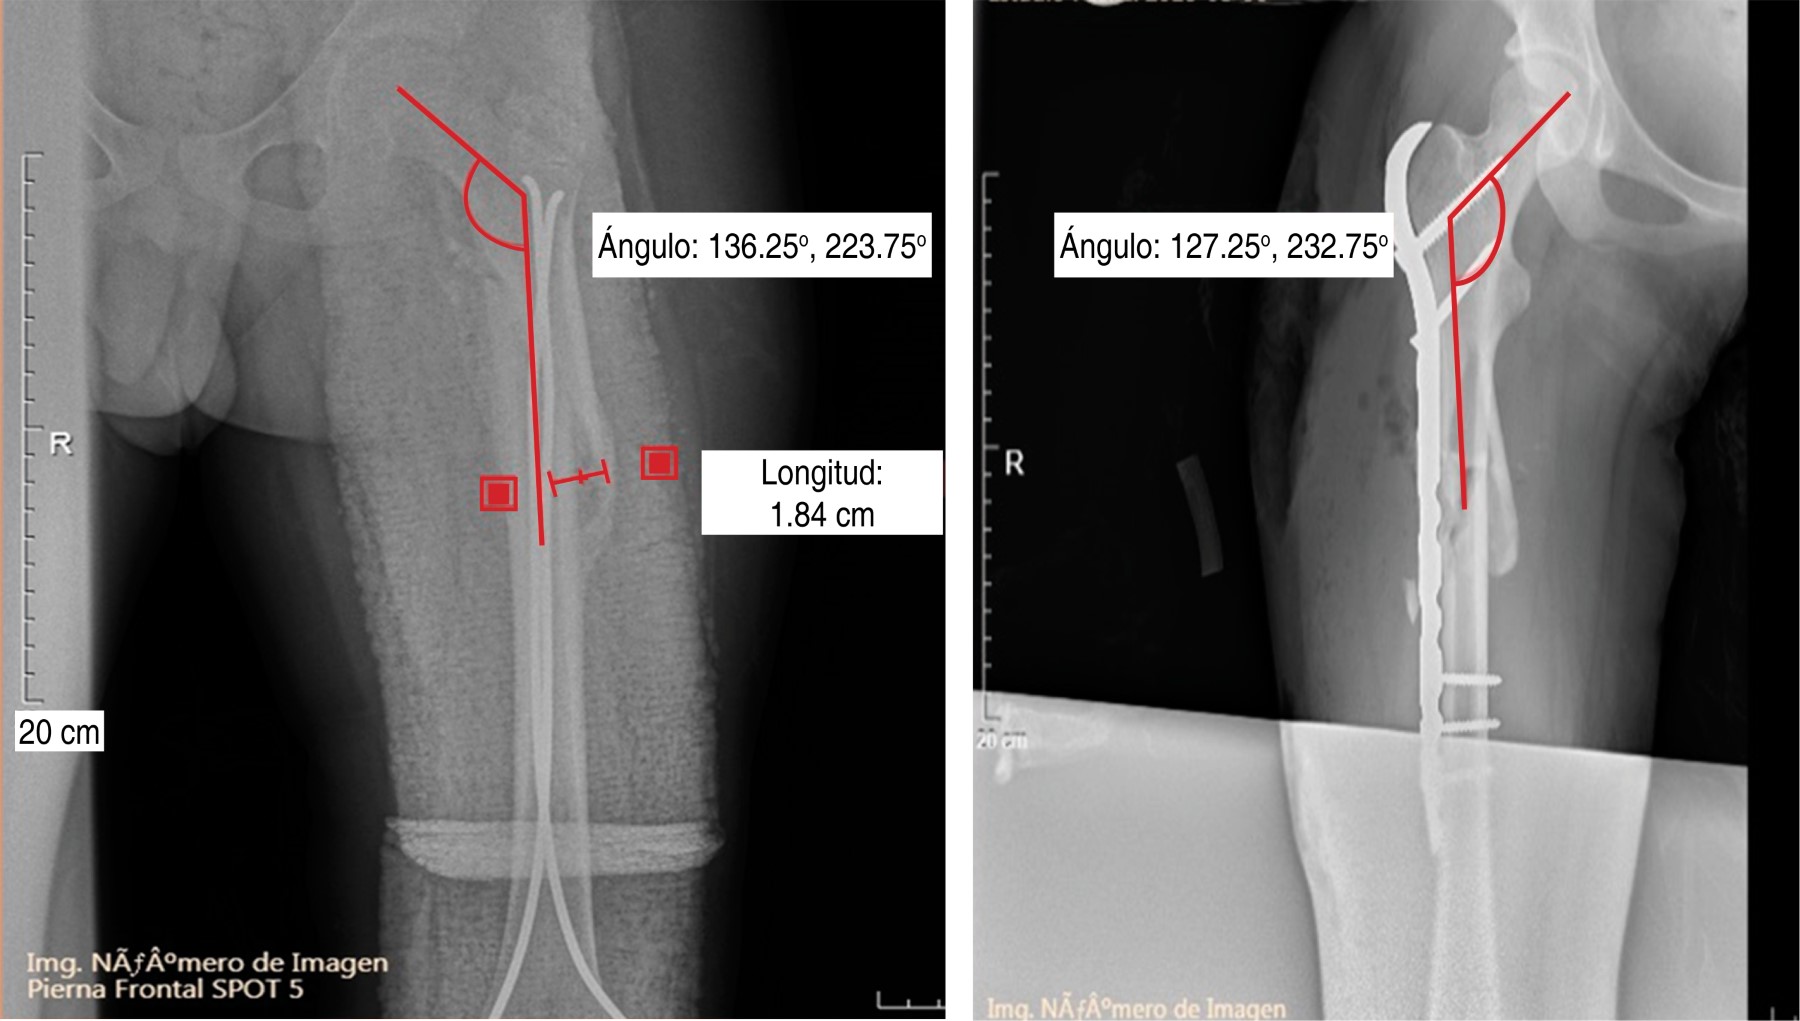

Se analizaron pacientes de 6 a 15 años con diagnóstico de fractura subtrocantérica de fémur, durante el periodo de 2017 a 2021 (Figura 1), se recabó un total de 23 pacientes, pero sólo 18 cumplieron los criterios de inclusión.

Se observó que los pacientes tratados mediante EEE presentaron una media de desplazamiento residual de 6 mm, mientras que los tratados por placa atornillada de fémur presentaron una media de 3 mm (Tabla 1).